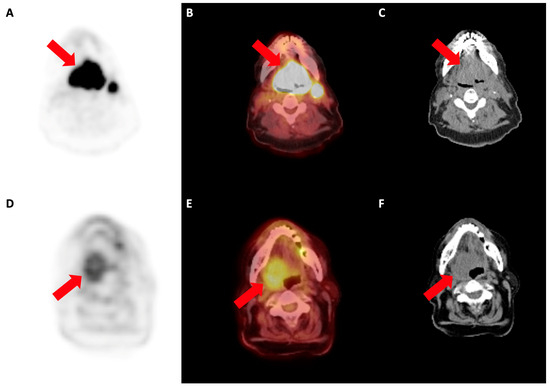

3.1. Prediction of Histology